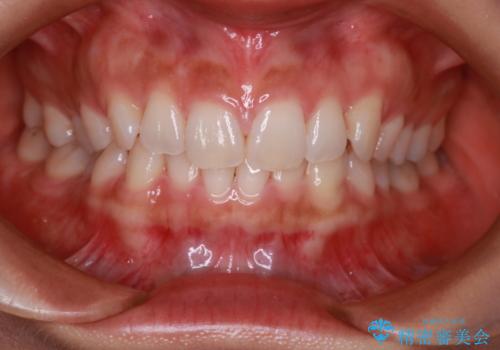

【インビザライン】前歯のねじれを治したい

- 前歯のガタガタを主訴に来院されました。

叢生の量は軽度でしたが臼歯の遠心移動を行い、インビザラインにて治療をしました。

叢生の改善に必要なスペースは遠心移動やIPRで作ることが可能です。今回は遠心移動をメインにスペースを作って叢生の改善を行いました。